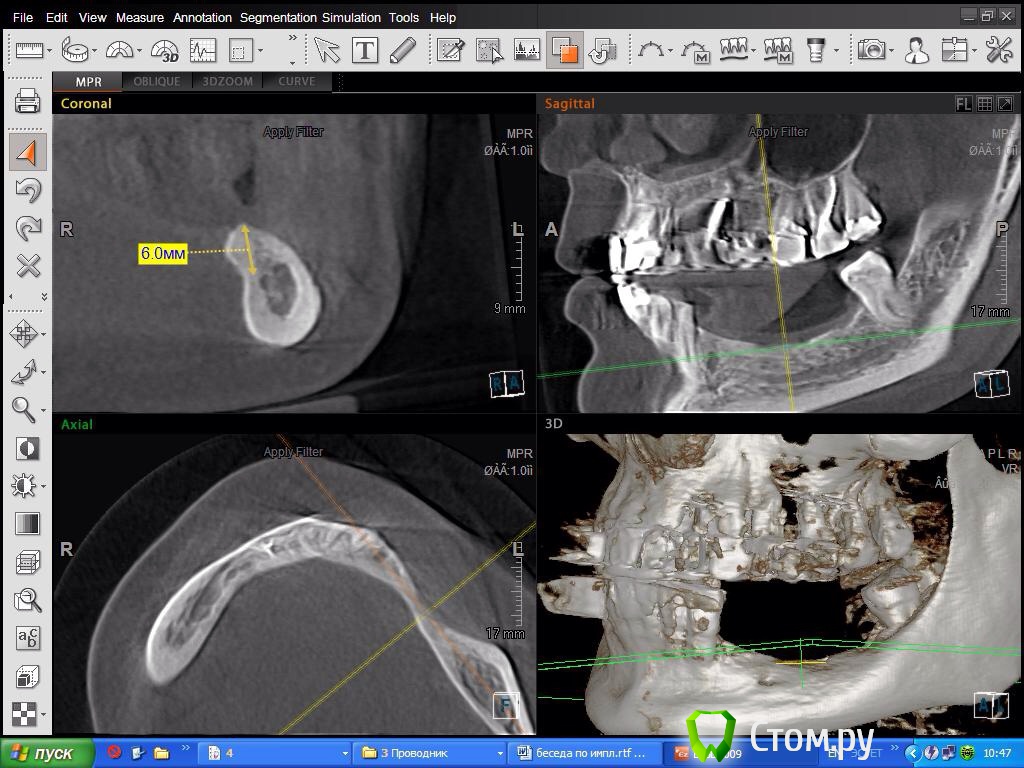

DoktorDre Опубликовано 8 октября, 2014 Поделиться Опубликовано 8 октября, 2014 (изменено) Коллеги - помогите. Имею небольшой опыт ламинатной техники, гбр , расщепления. Планируемая работа- импланты 44-46 и 34-36. Смущают дырки металисов.....как их обойти??? Хотел делать по Кури.Посоветуйте, опытные хирурги! Изменено 8 октября, 2014 пользователем DoktorDre Ссылка на комментарий

DoktorDre Опубликовано 8 октября, 2014 Автор Поделиться Опубликовано 8 октября, 2014 (изменено) Спасибо!Это все замечательно! Как обойти торчащие вверх металисы?? Не прикручу же на них ламинат!Особенно меня смущает 45-не расщепить, и металис совсем близко Изменено 8 октября, 2014 пользователем DoktorDre Ссылка на комментарий

DoktorDre Опубликовано 8 октября, 2014 Автор Поделиться Опубликовано 8 октября, 2014 Почему не расщепить? ,,,1) Будет сдавлен менталис в обл 45 2) много коркиткалки- плохо щепится 3) дефицит по вертикали только усугубится после расщепления 1 мм как правило уходит.. Ссылка на комментарий

DoktorDre Опубликовано 9 октября, 2014 Автор Поделиться Опубликовано 9 октября, 2014 Думаю, если покрутить КТ, то можно ещё не один вариант решения проблемы найти. В области первых премоляров проблемы вообще не вижуПоясните, почему не видите? Можно легко отслоится тупым путем, растягивая слизистую и не порвать менталис? Ссылка на комментарий